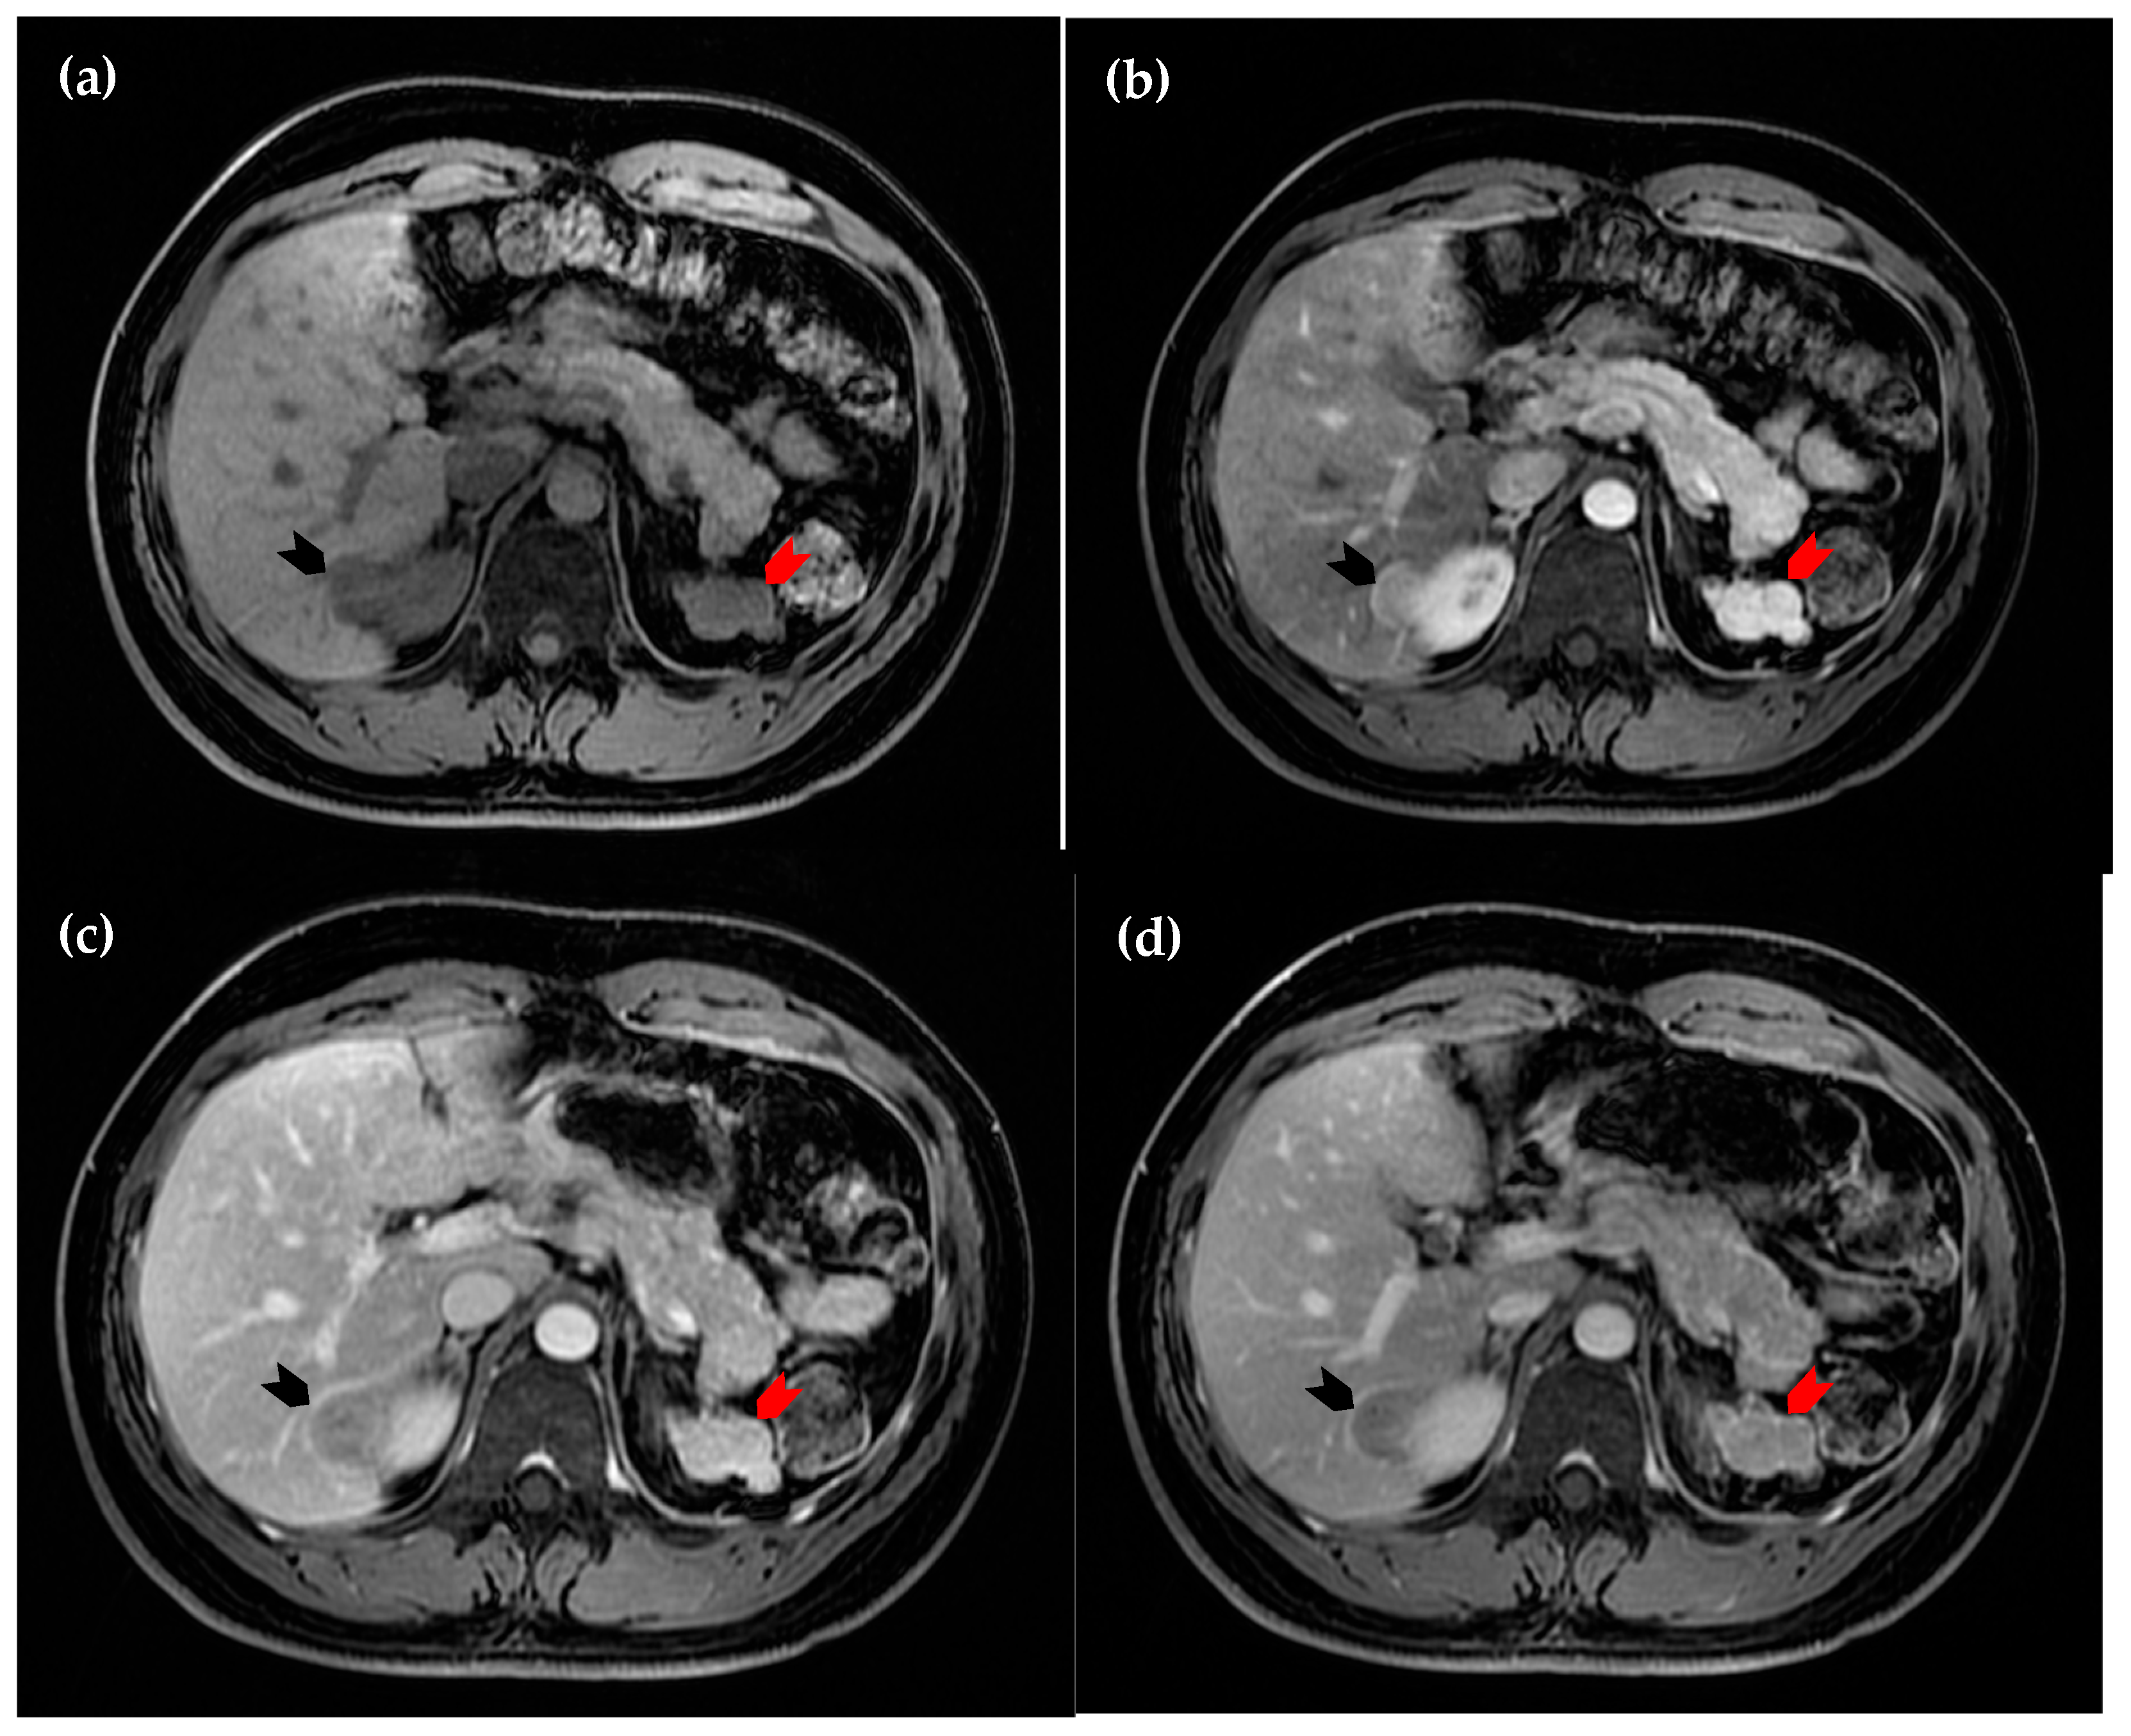

Figure 3. Dynamic magnetic resonance imaging of the liver. (a) Axial view of the pre-contrast sequence, in which the intrahepatic lesion is hypointense (black arrowhead); (b) axial view of the arterial phase, in which the lesion demonstrates homogeneous hyperintensity (black arrowhead); (c) axial view of the portal phase, in which early wash-out of enhancement is observed (black arrowhead); (d) axial view of the delayed phase, in which the lesion (black arrowhead) remains more hypointense compared to the surrounding hepatic parenchyma. The perinephric lesion again demonstrates similar attenuation across all sequences (red arrowhead in (ad)). However, due to the suspicious enhancement pattern of the intrahepatic lesion, a hepatic tumor cannot be excluded [1,2,3,4].